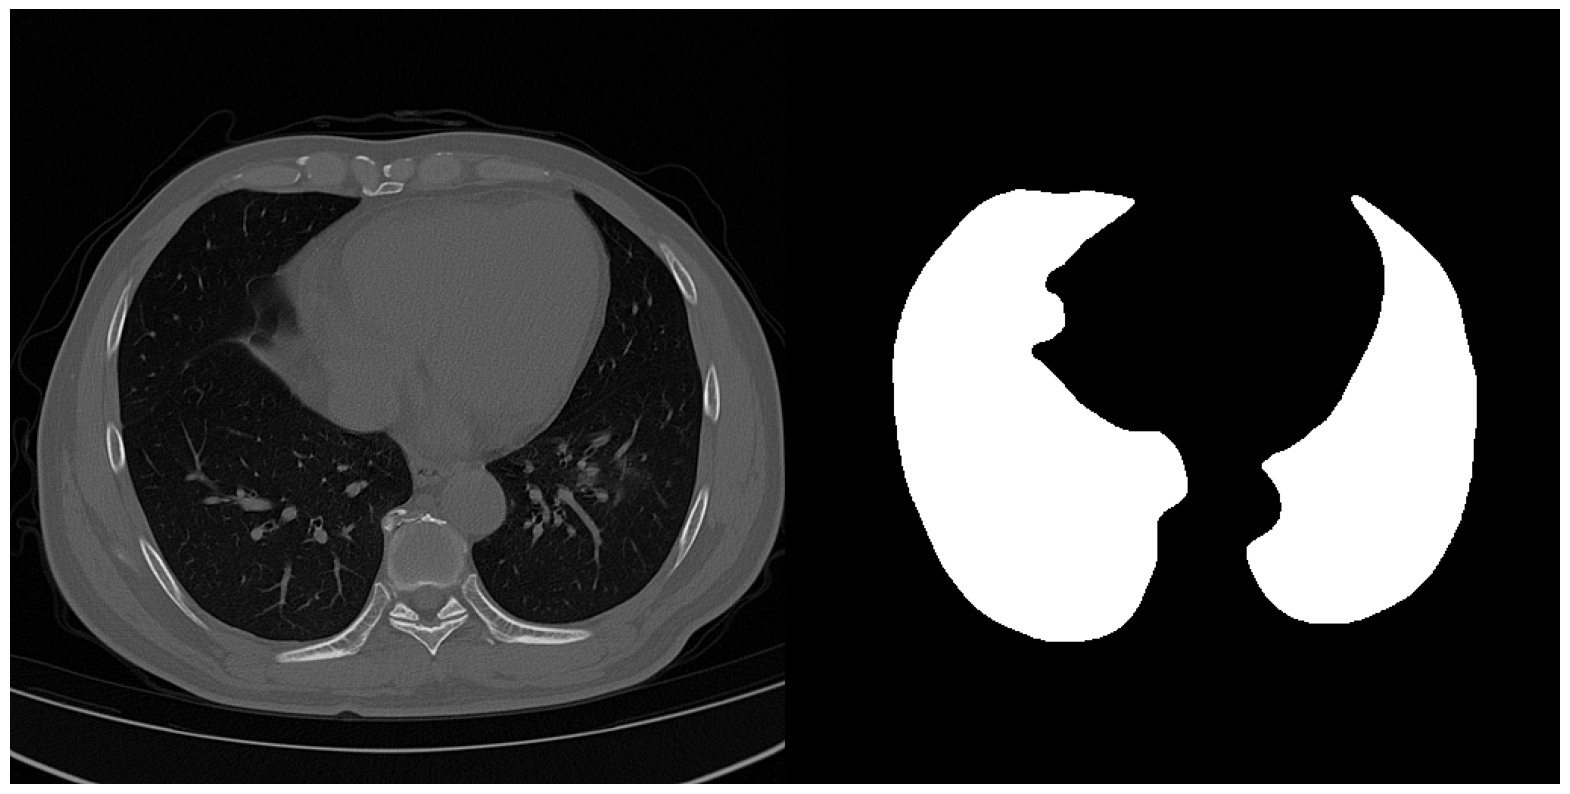

6.5.3 Validation with LUNG

The LUNG dataset is a collection of axial view lung CTs from three sources. The training and validation set consists of approximately 4000 slices extracted from 111 patient CT volumes from Pulmonary Fibrosis Progression (PFP), with their ground truth lung masks available in “CT Lung & Heart & Trachea segmentation” in Kaggle. We adopt another 90 axial view slices of lung CT volumes from “COVID-19 CT scans” showing lung with pneumonia as naturally occurring OOD data. (Access details in Section 4) The difference in the appearance of the COVID slices from the training set results not only from different imaging parameters but also from different infections. Each image is processed to have dimension 256×256256256256\times 256. We report below the mean IOUs and SBI of models trained on different models.

Refer to caption

(a) Image from "OSIC Pulmonary Fibrosis Progression" [38, 39]

(b) Image from "COVID-19 CT scans" [40, 41, 42]

(c) The image from "OSIC Pulmonary Fibrosis Progression" with (from left to right) Gaussian noise, shot noise, impulse noise, and defocus blur applied.

Figure 14: Samples from the three partitions of data domain in FISH

Augmentations, however, have negligible effects on this dataset. We explain this phenomenon by arguing that non-shape features may persist across multiple domains for LUNG. In LUNG, pixels associated with the lung have a texture style easily distinguishable from those associated with the rest of the image. The cooccurrence of high-intensity contours formed by cartilages also helps locate the lung. These features persist even across different image domains. In this case, the shape may not be the best discriminative feature in prediction capability. Non-shape features may be the more desirable feature sets to learn when optimizing the Cross-Entropy objective function. To avoid overstretching on interpreting the results, we will stop here with the conclusion that though Color Jitter and NST may suppress non-shape features, they barely hurt a model’s generalizability on Noisy and OOD data.